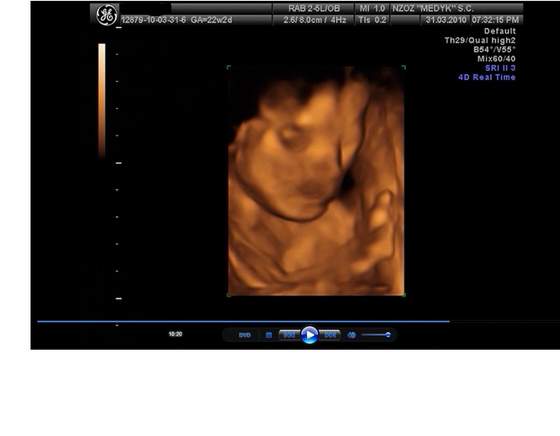

Gratuluję córunia pięknanasza Córcia się do nas uśmiecha (22tc):

nasza Córcia sie do nas uśmiecha (22tc):

uśmiecha się, uśmiecha, piękności Marto...;-);-)